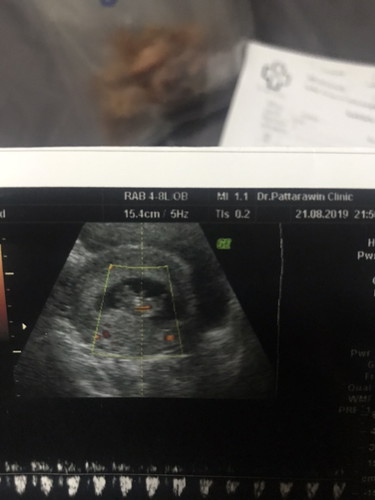

นี่รูปตอนซาว9+5wค้ะแม่ หมอตรวจทั้งพ่อและก็แม่พร้อมกันเรยค้ะ ปกติดีค้ะ ขอไห้แม่สู้ๆน้ะค้ะเเข็งแรงๆจ้า